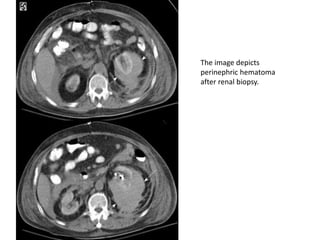

The image depicts

perinephric hematoma

after renal biopsy.

Bleeding may occur in 3 distinct locations within the kidney: into the collecting system,

under the renal capsule, or into the perinephric space.